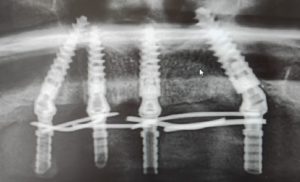

All-on-4 / All-on-6 implantátumok

Ha részleges vagy akár teljes foghiányban szenved, nem kell többé feszélyezve éreznie magát étteremben, mindennap átélnie a műfogsor ragasztó okozta kellemetlenségeket vagy akár azon aggódnia nevetés közben, hogy mosolya nem a régi. Fogsora stabil marad a beültetett 4 vagy 6 implantátumnak köszönhetően.

Az all-on-4 esetében négy, speciálisan tervezett implantátumot helyezünk el az állcsontban, általában kettőt elöl és kettőt hátul. Ezek a beültetett implantátumok adnak egy stabil alapot a rögzített fogpótlás számára. Előnye, hogy kevesebb beavatkozásra és implantátumra van szükség, így gyakran rövidebb a gyógyulási idő és a költségek is alacsonyabbak lehetnek.

Az all-on-6 esetében, ahogy a neve is mutatja, hat implantátumot használnak a fogpótlás rögzítéséhez. Mivel több implantátumot használnak, gyakran stabilabb, erősebb rögzítést biztosít, ami ideális lehet, ha nagyobb rágóerőre van szükség.

Az, hogy Önnek melyik a legjobb választás függ az állkapocsban rendelkezésre álló csont mennyiségétől és az egyéni preferenciáktól is. Egy dolog azonban biztos: mindkét módszerrel visszakaphatja azt az érzést, amit az elveszett fogak okoztak és újra bátran mosolyoghat!

| All-on-4 NeoArch® Implantáció fejrészekkel (azonnal terhelhető) / állcsont | 1 390 000 Ft | 3 660 € |

| All-on-6 NeoArch® Implantáció fejrészekkel (azonnal terhelhető) / állcsont | 1 700 000 Ft | 4 475 € |